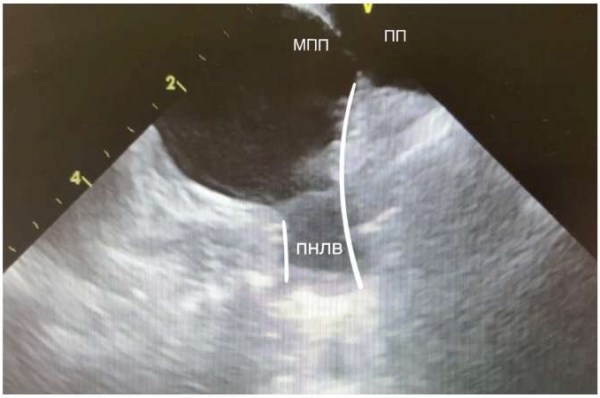

Рис. 7. Правая нижняя ЛВ. Межпредсердная перегородка, переходящая на нижнюю стенку правой нижней ЛВ (выделено белым контуром).

Сокращения: МПП — межпредсердная перегородка, ПНЛВ — правая нижняя легочная вена, ПП — правое предсердие.